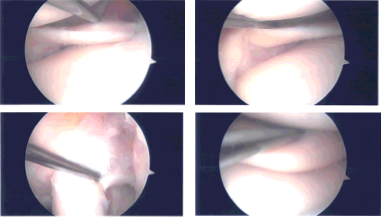

A lateral entry portal was made and arthroscope was inserted. A medial entry portal was made with the use of spinal needle. Examination of the knee showed arthritic changes in the medial femoral head as well as tearing of the medial meniscus along the anterior horn.

No tear could be found in the posterior horn, posterior root as well as posterior body of the medial meniscus.

Debridement of the medial meniscus of the anterior horn was performed with the use of shaver. Chondroplasty of the medial femoral condyle was also performed with the use of a shaver. Examination of the intercondylar notch showed intact ACL with degeneration.

Examination of the lateral compartment, tibiofemoral compartment showed intact lateral meniscus as well as bilateral tibiofemoral compartment. Examination of the patellofemoral compartment showed grade 3 to grade 4 osteoarthritis of the trochlea as well as inferior surface of patella.

Debridement of the patellofemoral joint was performed with the use of shaver. Abrasion chondroplasty was also performed with shaver along as well as the patella. Final pictures were taken for safety. The knee was thoroughly irrigated.

Intraoperative Arthroscopy Images